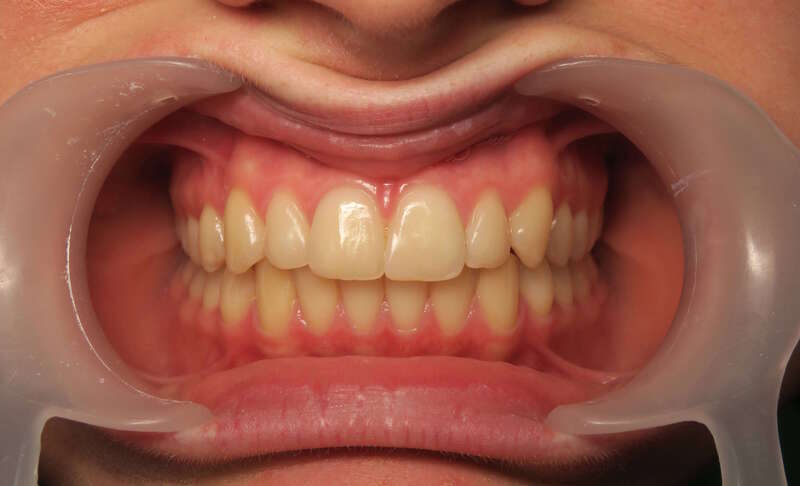

Cas n°1 traité par aligneurs - adolescent

Ce cas d’une adolescente illustre la correction d'une Classe II avec supraclusion par aligneurs. La stratégie thérapeutique a reposé sur une distalisation séquentielle de l'arcade supérieure. Ce mouvement précis a permis de reculer les dents maxillaires étape par étape pour annuler le surplomb (overjet) sans extractions.

Résultats clés :

• Correction fonctionnelle : Retour à un engrènement de Classe I stable et correction du recouvrement vertical.

• Esthétique restaurée : Harmonisation globale du sourire et du profil.

• Approche moderne : Un traitement discret, confortable et hautement prévisible.

Le résultat final montre une occlusion saine et un sourire parfaitement aligné, garantissant une santé dentaire et articulaire optimale pour l'avenir.